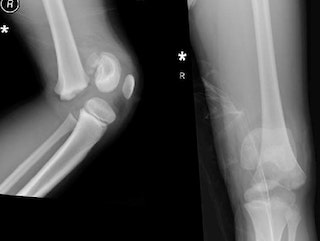

- Рентгенография позвоночника: Это основной метод первичной диагностики компрессионного перелома. Выполняется в двух проекциях (прямой и боковой) для оценки формы и высоты тел позвонков. Рентген покажет степень компрессии и наличие клиновидной деформации.

- Компьютерная томография (КТ): Может быть назначена для более детальной визуализации костных структур позвонка, оценки степени разрушения и исключения фрагментации. КТ информативна для выявления скрытых повреждений.